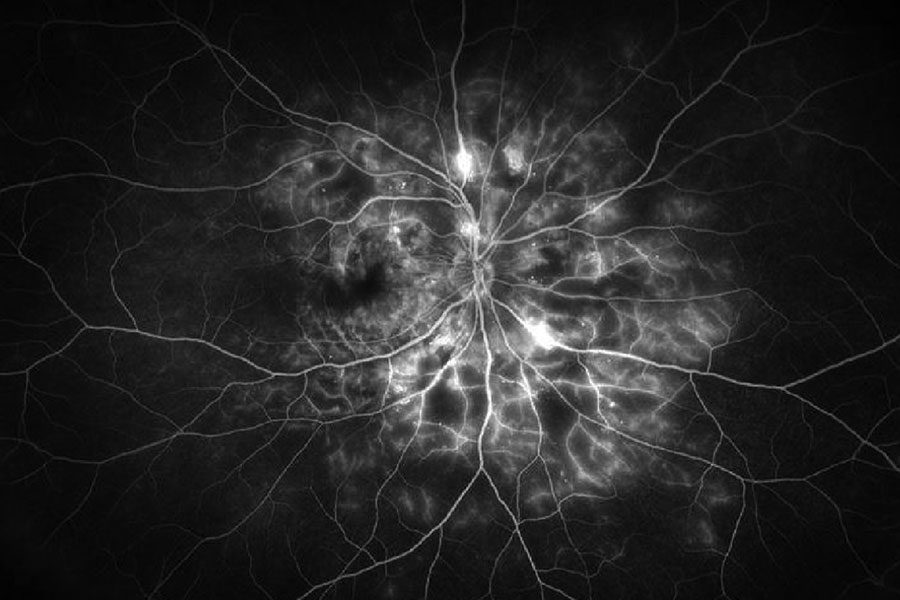

| Figura 4. Imagen de angiografía con fluoresceína de campo amplio del ojo derecho de un paciente con retinopatía diabética proliferativa, que muestra áreas hiperfluorescentes de tinción vascular y fuga junto con áreas hipofluorescentes de no perfusión capilar. Foto: Jason Hsu, MD. |